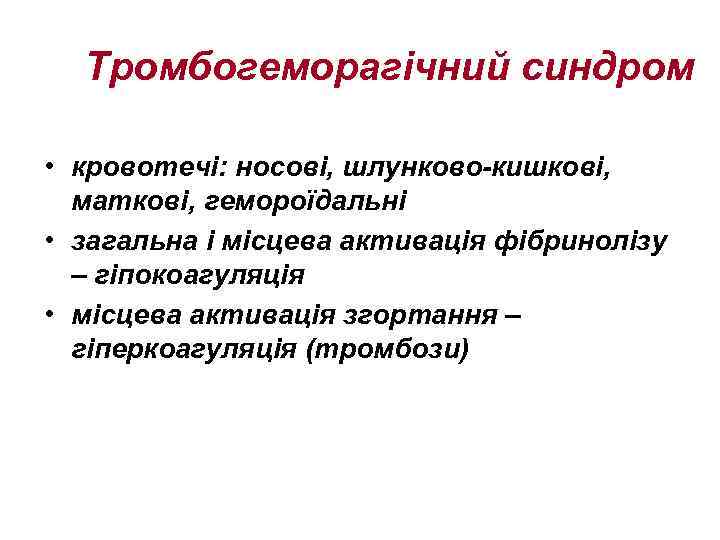

Тромбогеморагічний синдром • кровотечі: носові, шлунково-кишкові, маткові, гемороїдальні • загальна і місцева активація фібринолізу – гіпокоагуляція • місцева активація згортання – гіперкоагуляція (тромбози)

Тромбогеморагічний синдром • кровотечі: носові, шлунково-кишкові, маткові, гемороїдальні • загальна і місцева активація фібринолізу – гіпокоагуляція • місцева активація згортання – гіперкоагуляція (тромбози)